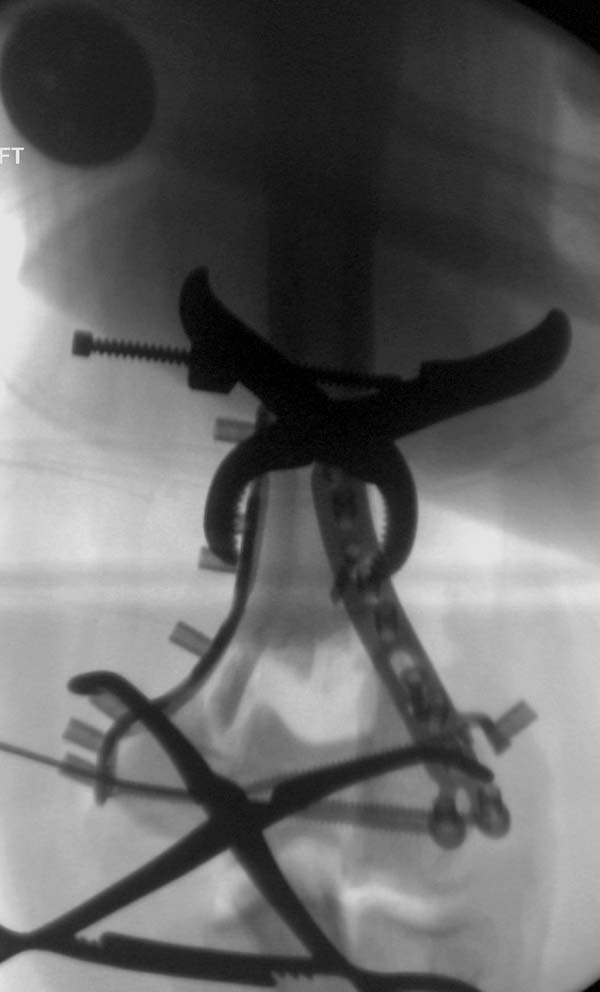

Примеры: первому более 15 лет фиксирован шурупом и tension band

technique, а второй перелом открытый больной 80 лет, после наружного

фиксатора в первом этапе и окончательная фиксация вторично. Третьий раз

внесуставная остеотомия...

Имя     : 3-2 Humerus prox distal exfix.jpg

Тип     : image/jpeg

Размер  : 43483 байтов

Описание: отсутствует

Url     : http://weborto.net:8080/pipermail/ortho/attachments/20130604/c45a379f/attachment-0028.jpg